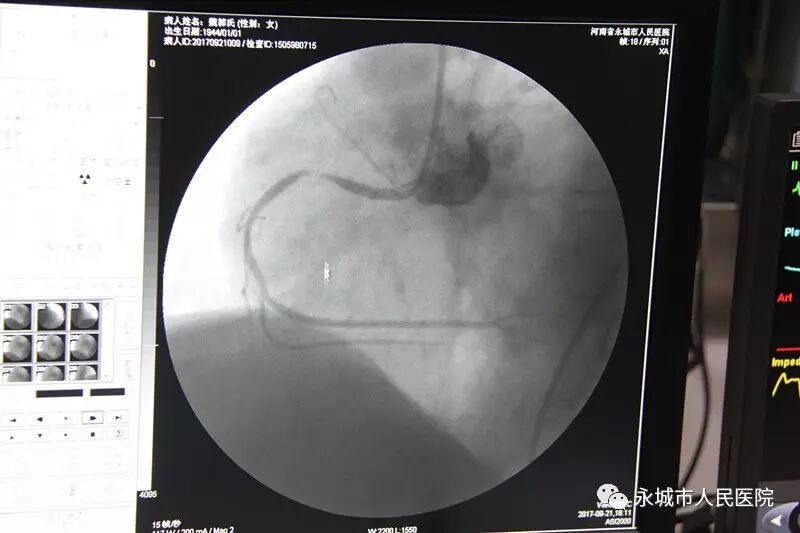

2017年9月21日下午,永城市人民医院急诊PCI救治了一位急性心肌梗死的病人,女性,魏某某,73岁,心电图显示——急性下壁ST段抬高性心肌梗死。情况紧急。

导管室主任朱珂带领医护团队密切配合,严格按照操作规程,5分钟完成穿刺造影。

估计狭窄95%,决定植入支架1枚。

支架贴壁良好,向前血流TIMI3级,手术成功,整个过程40分钟。

本次手术整个导管室团队密切配合。期间导丝通过闭塞病变时,患者出现了再灌注心律失常,心率血压持续性下降,开通堵塞血管,出现再灌注心律失常是开通血管成功标志之一,我们的团队临危不乱,最终和患者一起战胜了困难,守护了生命。